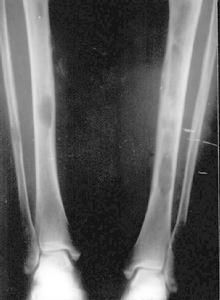

5.骨變形 由於維生素D缺乏 繼發甲狀旁腺功能亢進所致骨骺脫位,使長骨變彎,常波及臀部,也可見於橈骨、尺骨、肱骨下端、股骨下端和脛骨下端。

放射學檢查:繼發性甲狀旁腺功能亢進的放射學改變包括骨內膜、骨皮質和骨膜下的骨吸收,終端指、趾骨的腐蝕,囊腫形成,骨膜的neostosis和骨硬化,其中骨膜下骨吸收是最常見的放射學改變,主要見於指骨, 還可見於骨盆骨、鎖骨遠端以及肋骨、尺骨、脛骨和下頜骨下方的表層。骨硬化的放射學改變,為骨的密度增加,常見於椎體 骨盆、肋骨、鎖骨和各種長骨的乾骺端, 骨軟化的診斷有賴於骨活檢。放射學的惟一發現是Loosers帶的出現和假性骨折,骨密度常降低,但不足以診斷骨軟化。骨質減少是指放射學檢查發現的骨密度減低,常見於長期腎功能衰竭做血透治療者。骨軟化、繼發性甲狀旁腺功能亢進和骨質疏鬆經放射學檢查都可發現骨密度減低,很難單憑放射性特點來判斷骨質減少的原因。